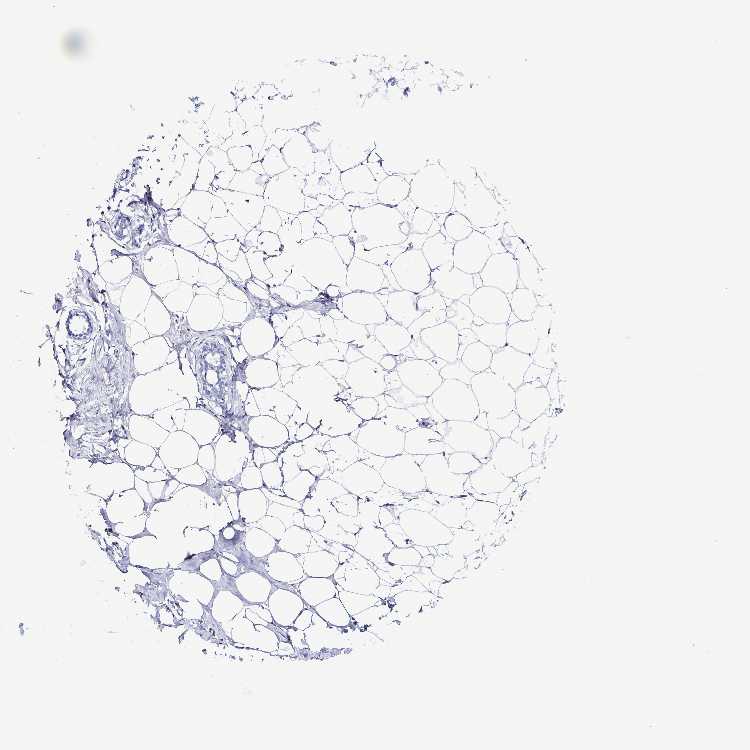

BREAST - Antibody stainingi

Antibody staining in the annotated cell types in the current human tissue is reported as not detected, low, medium, or high, based on conventional immunohistochemistry profiling in selected tissues. This score is based on the combination of the staining intensity and fraction of stained cells.

Each image is clickable and will lead to virtual microscopy that enables deeper exploration of all samples and also displays staining intensity scores, fraction scores and subcellular localization as well as patient and tissue information for each sample.

Antibody HPA051368Antibody HPA061671

Adipocytes Not detectedNot detected

Glandular cells Not detectedNot detected

Myoepithelial cells Not detectedNot detected